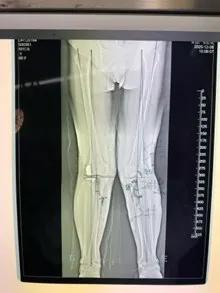

經(jīng)過(guò)詳細(xì)的體格檢查、影像學(xué)評(píng)估和三維重建,醫(yī)療團(tuán)隊(duì)確認(rèn)鮑奶奶的情況非常適合進(jìn)行膝外側(cè)單髁置換術(shù)。這種微創(chuàng)手術(shù)創(chuàng)傷小、恢復(fù)快,能夠最大程度保留膝關(guān)節(jié)的自然結(jié)構(gòu)和功能。

手術(shù)當(dāng)天,骨科團(tuán)隊(duì)采用微創(chuàng)切口,僅約8厘米,遠(yuǎn)小于傳統(tǒng)全膝關(guān)節(jié)置換手術(shù)切口。術(shù)中精準(zhǔn)定位,僅置換病變的膝關(guān)節(jié)外側(cè)間室。

手術(shù)使用了最新的單髁假體系統(tǒng),這種假體設(shè)計(jì)更符合人體工程學(xué),能夠更好地恢復(fù)膝關(guān)節(jié)的自然運(yùn)動(dòng)軌跡。

整個(gè)手術(shù)過(guò)程僅持續(xù)約1小時(shí),術(shù)中出血不到100毫升。術(shù)后鮑奶奶被送回病房,生命體征平穩(wěn)。